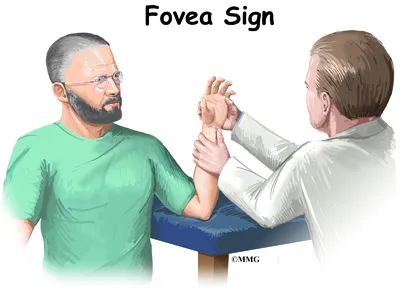

Triangular fibrocartilage complex (TFCC) injuries affect the ulnar side of the wrist—the side closest to the little finger. Mild cases may feel like a simple wrist sprain, but due to the complexity of the wrist’s soft tissues, these injuries can significantly impact stability and function.

The TFCC plays a crucial role in supporting and stabilizing the wrist joint, allowing smooth and controlled movement. When this structure is damaged through trauma or gradual degeneration, it can lead to persistent pain, weakness, and limited mobility.